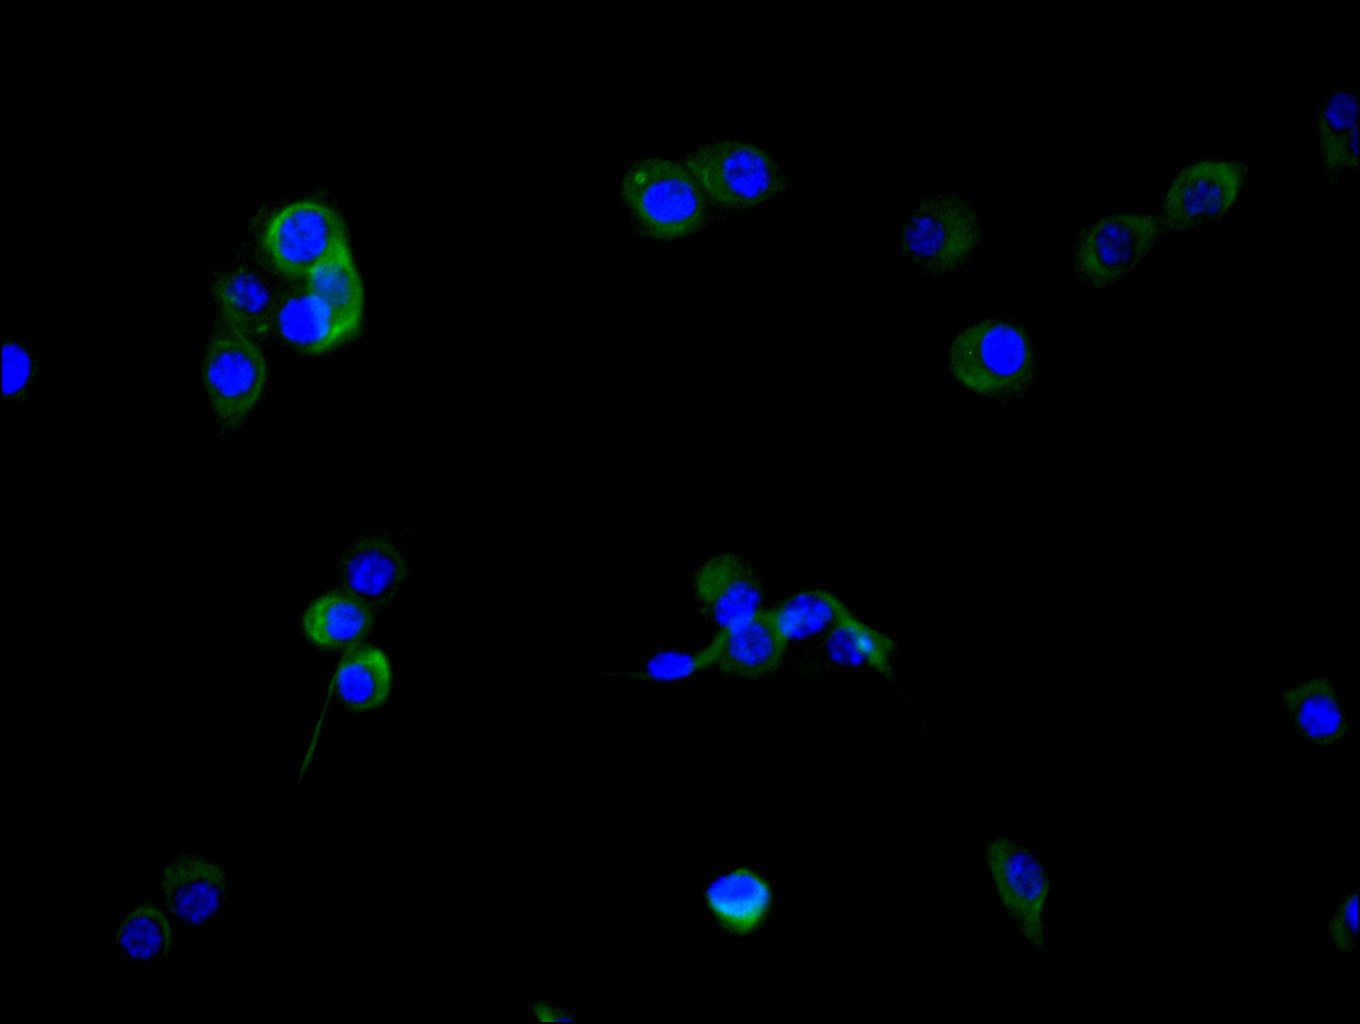

5. FAP研究工具

FAP作為腫瘤微環(huán)境中的關(guān)鍵靶點(diǎn),其在腫瘤的侵襲、轉(zhuǎn)移、免疫逃逸以及耐藥性中發(fā)揮重要作用。華美生物提供FAP重組蛋白、抗體及ELISA試劑盒產(chǎn)品,助力您開(kāi)發(fā)特異性靶向FAP的藥物,探索其在腫瘤治療中的應(yīng)用潛力。